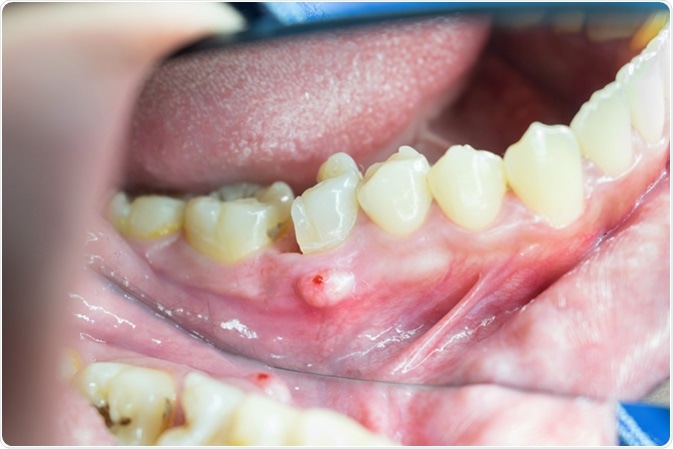

Image Credit: Trailak Amtim / Shutterstock